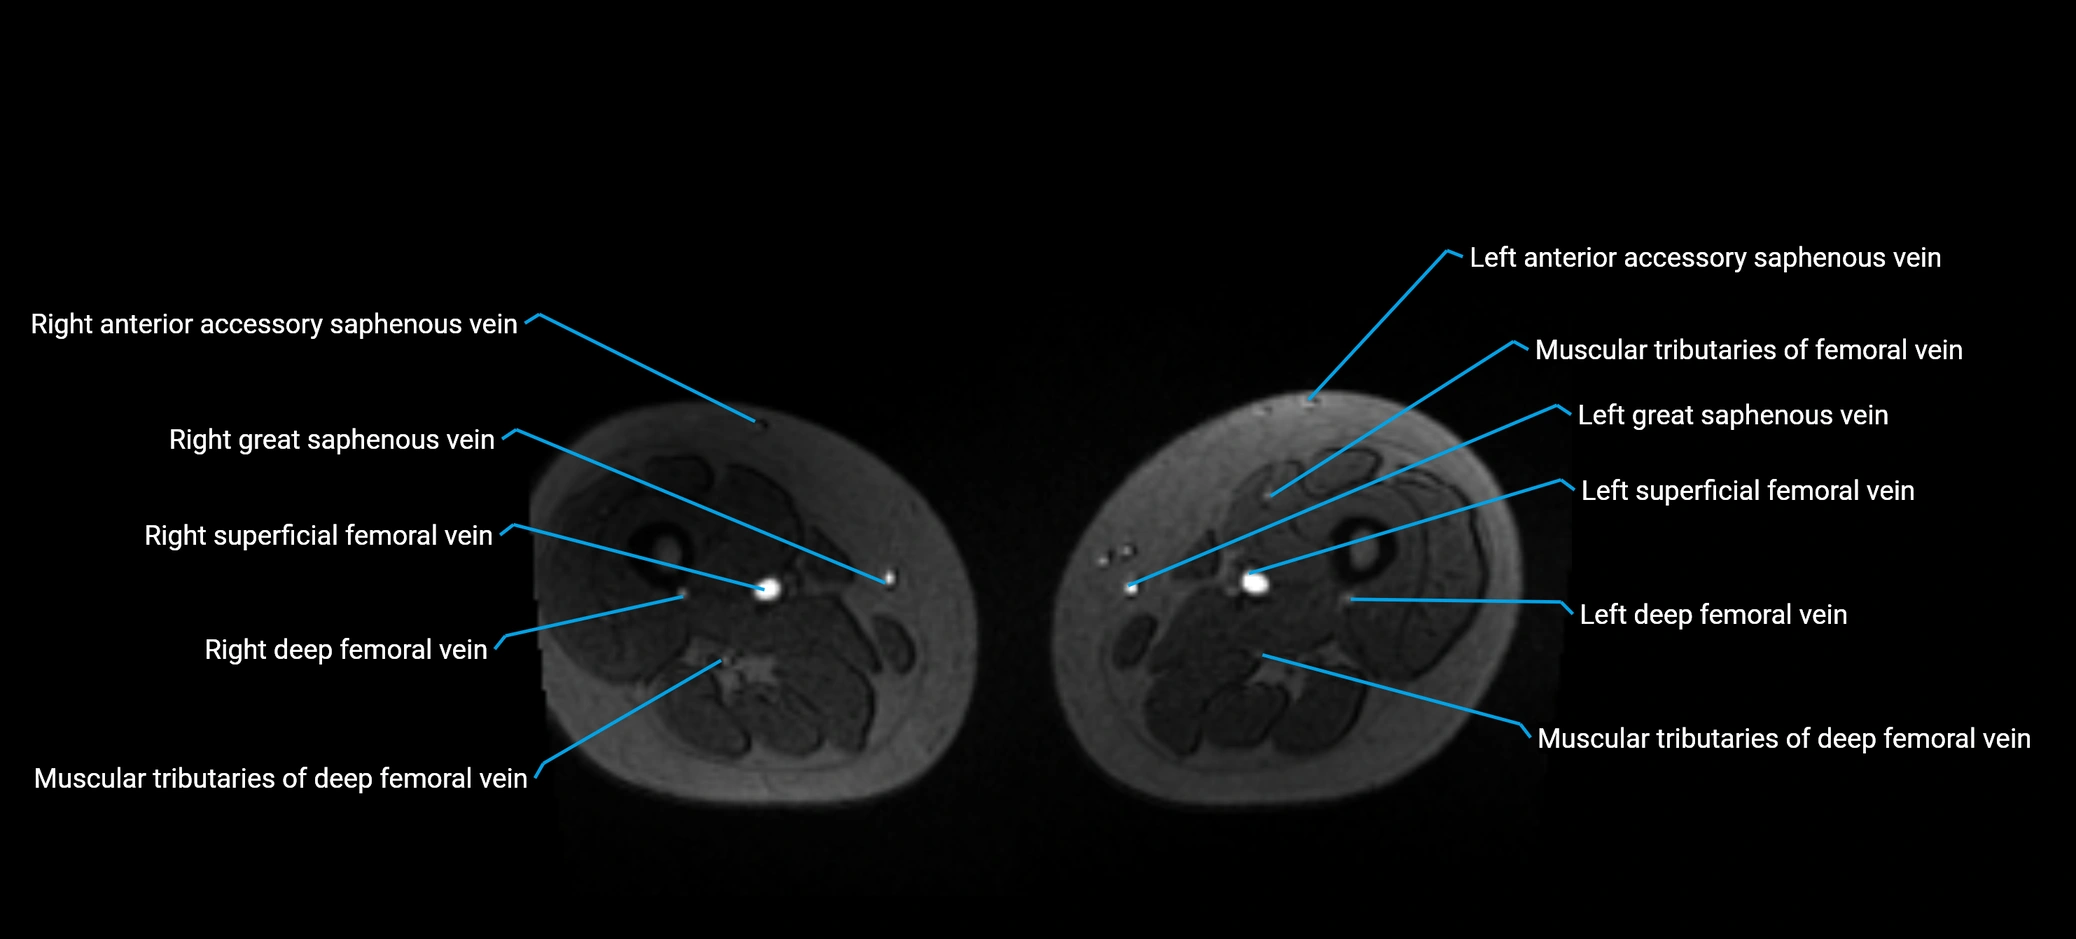

MRV TOF (Time-of-Flight MR Venography):

• Appears as a bright, high-signal vascular channel representing flowing blood

• Clearly shows branching pattern of right portal vein into anterior and posterior branches

• Best in coronal or axial reconstructions for segmental mapping

• No need for contrast, relies on flow-related enhancement